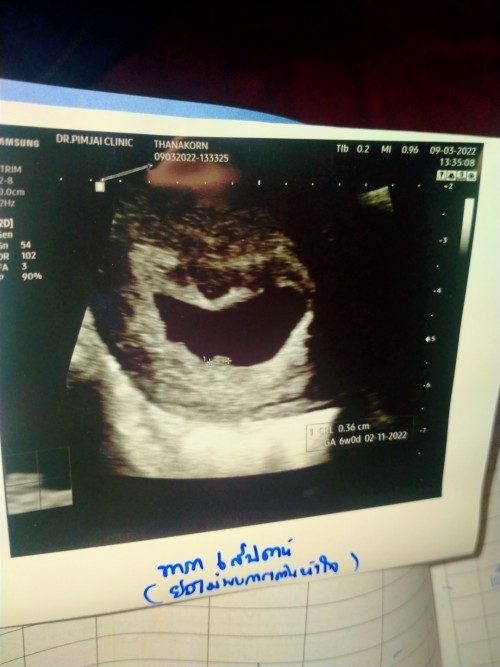

แม่ๆ ซาว์ดเจอ ตัวเล็ก ตอนกี่วิคค่ะ แม่บ้านนี้ ซาวด์ตอน 7วิค ลุงหมอบอกยังไม่เจอตัวเล็กเลย เจอแต่ถุงตั้งครรภ์ #แอบกังวลนิดๆ #ขอบคุณสำหรับคำตอบค่ะ

ซาวทางช่องคลอดครั้งแรกตอน 4 W เห็นถุงตั้งครรภ์ หมอนัดอีกที 6 W ซาวทางช่องคลอดเจอตัวน้องแล้วค่ะ ได้ฟังเสียงหัวใจเต้นด้วย

บ้านนี้เจอ 9w ค่ะ ช่วง 7w ไปซาวด์ก็เจอแต่ถุงตั้งครรภ์ค่ะ รออีกนิดเดี๋ยวก็เจอค่ะ